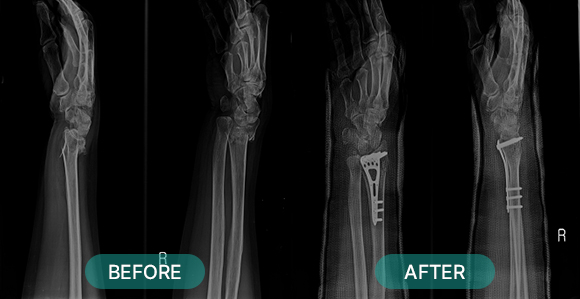

관혈적 정복이란 골절된 부위를 절개하고 뼈를 노출시켜 눈으로 직접 보면서 골절편을 정확하게 맞추는 방법으로 금속판과 나사 고정법, 핀고정법, 나사고정법, 골수 내정 고정법, 인공 관절 치환술, 외고정 기구 고정법 등등 여러 방식이 있습니다.

- 콜레스 골절, 복서 골절